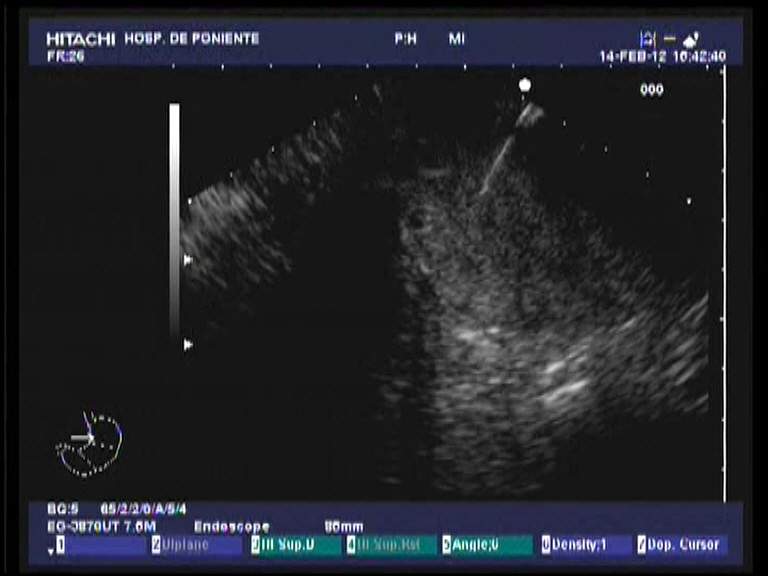

Paciente de 69 años de edad con antecedentes de HTA, fibrilación auricular permanente y DM tipo II en tratamiento con insulina Ingresa en digestivo por cuadro de ictericia franca de piel y mucosas, coluria y acolia junto a cuadro constitucional de un mes y medio de evolución. Molestias epigástricas inespecíficas. Febrícula asociada en las últimas 48 horas. Analíticamente destaca una BRT de 20 mgr/dl a expensas de la fracción directa con marcada elevación de las enzimas de colestasis. GOT y GPT elevadas con predominio de la segunda unas 5 VN. No elevación de los marcadores tumorales habituales (CEA, Ca-19.9, Ca-15.3, CA-125). En las pruebas de imagen realizadas (ECO, TAC) se aprecia una gran masa de localización retroperitoneal, isoecogénica, de 9 x 12 cm que desplaza al páncreas, contacta y estenosa la luz duodenal a nivel de la 2ª porción, infiltrando el área papilar, junto a una marcada dilatación difusa del conducto pancreático, así como del colédoco (17 mm) y de la vía biliar intrahepática. Se realiza CPRE, consiguiendo el acceso biliar mediante una esfinterotomía transpancreática tipo II, con drenaje biliar eficaz mediante la colocación de una prótesis completamente recubierta de 6 cm de longitud. Las biopsias de la papila, de aspecto endoscópico infiltrado, mostró células atípicas inespecíficas. Se decidió realizar una USE-PAAF, sin diagnóstico concluyente. Se decidió finalmemte realizar una intervención de Whipple. El estudio histológico de la pieza quirúrgica fue compatible, con técnicas de inmunohistoquímicas específicas (synaptophysina y cromogranina A), con un tumor neuroendocrino no funcionante de estirpe no especificada.

Los tumores neuroendocrinos del páncreas son raros (< 10 % del total de todos los tumores pancreáticos). Pueden ser funcionantes, como los insulinomas, glucagonomas, vipomas y gastrinomas o no. Estos últimos son bastante mas frecuentes que los primeros, dentro de su rareza global. Los tumores funcionantes dan síndromes específicos acorde a la hormona secretada y pueden ser benignos o malignos, incluso con metástasis a distancia (hepáticas sobre todo). Los no funcionantes, se diagnostican de forma causal al realizar una ECO/TAC por otras razones o bien por la aparición de un cuadro constitucional con ictericia. La mayoría de los no funcionantes asientan en la cabeza pancreática. Ecográficamente son iso-hipoecogñenicos. La USE-PAAF con tinciones de inmunohistoquímica permiten el diagnóstico (sobre todo para la synaptophysina) en la mayor parte de los casos (S: 85 %, E: 95 %, VPP: 95 %, VPN: 60 % y seguridad diagnóstica del 83 %). La malignidad está en relación directa al tamaño del tumor, con el desarrollo de metástasis regionales (linfáticas), infiltración de órganos vecinos (duodeno) y desarrollo de ictericia. El tratamiento quirúrgico es obligado en la totalidad de los casos.